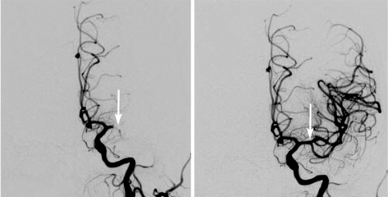

The procedure is made possible by image-guided catheters and a wire cage device, called a stent retriever, which are used to remove blood clots in large vessels in the brain. Liner threads the catheter through an artery in the groin up to the blockage in the brain. He then deploys the stent retriever through the clot and removes the stent retriever with the captured clot through the catheter that was placed in the artery.

“Ideally, the procedure should be done within six hours of symptom onset,” explains Liner. “However, a national study called the DAWN Trial and published in The New England Journal of Medicine, has proven it can still be effective if done within 24 hours of onset under certain conditions. This gives us a greater chance of helping people who wake up with stroke symptoms and don’t really know when they first started. More importantly, it’s more likely that patients will regain movement, speech or other abilities lost.”